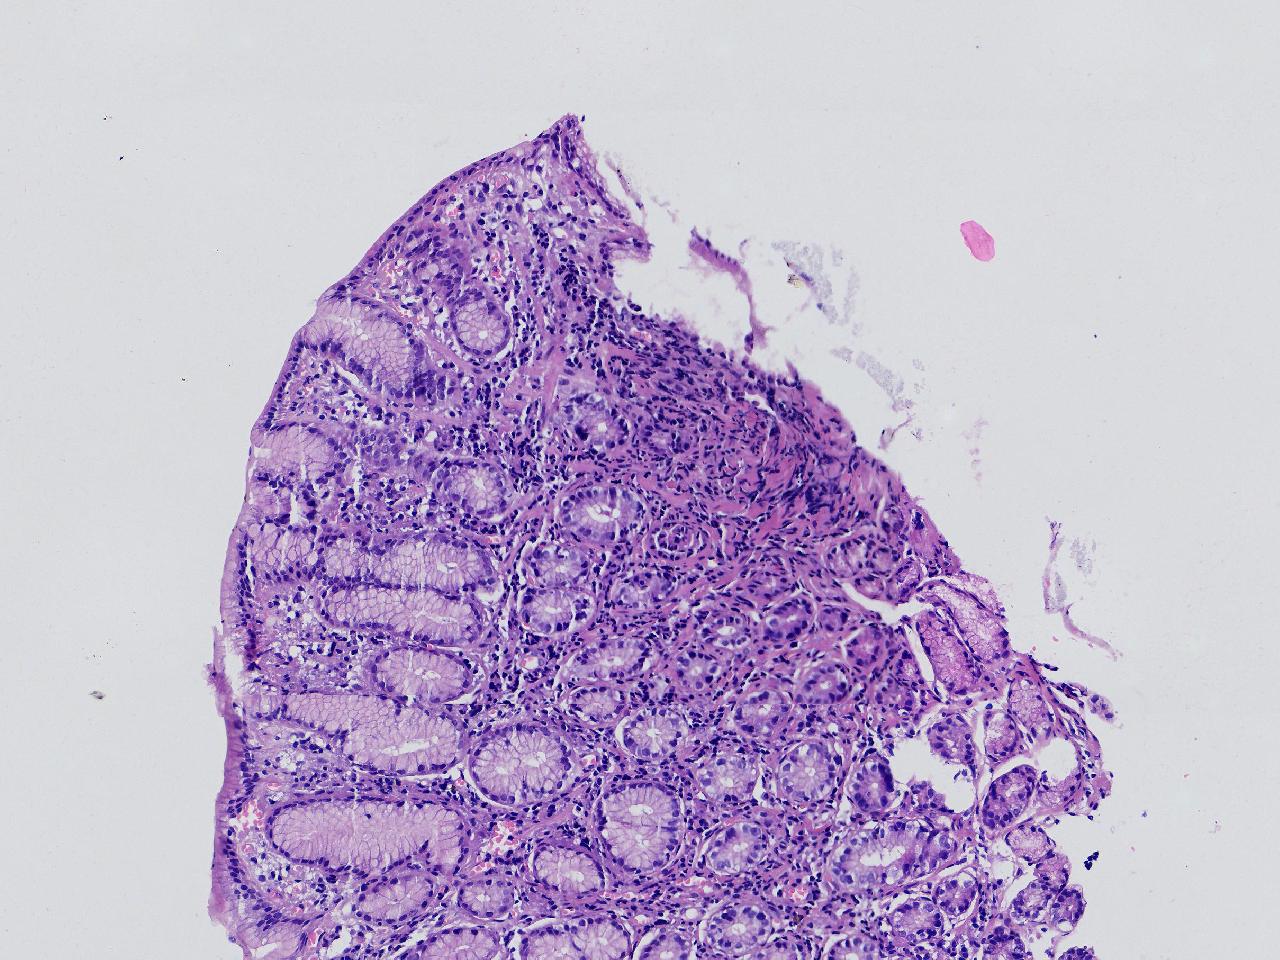

间质内是炎细胞吗?

男,49岁,胃镜活检,胃窦粘膜红白相间,以红为主,后壁见一直径约0.4cm大小片平隆起,表面糜烂,活检1块送检,质软弹性可。

胃窦活检

灰白色不整形软组织1块,直径0.2厘米。

是!还有组织细胞

幽门型粘膜中度慢性炎

是的,主要是淋巴细胞和浆细胞。